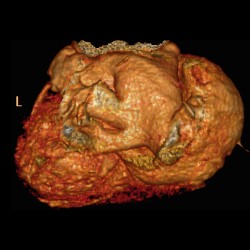

Giant Left Atrium Due to Rheumatic Mitral Regurgitation

Giant Left Atrium Due to Rheumatic Mitral Regurgitation

Giant Left Atrium Due to Rheumatic Mitral Regurgitation

Giant Left Atrium Due to Rheumatic Mitral Regurgitation